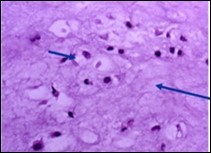

Characteristically, enchondroma is below < 5 centimetre magnitude although enlarged lesions can be considered benign when accompanying indeterminate or atypical microscopic features are absent4, 5. Enchondroma is composed of well-circumscribed nodules of benign hyaline cartilage. Incorporated chondrocytes demonstrate miniature, uniform, spherical nuclei with condensed chromatin. Bi-nucleate cells are infrequent4, 5.

Typically, chondroid matrix of an enchondroma depicts foci of punctate calcification. Tumour cell nuclei are fairly uniform. Mitotic figures are few. Extensively calcified enchondromas are associated with foci of endochondral ossification 4, 5.

The neoplasm is configured of lobules of hyaline cartilage enveloped by perichondrium-encased bone. Tumefaction can be hyper-cellular with bi-nucleate tumour cells. Myxoid change, foci of calcification and endochondral ossification are discerned. Necrosis may ensue on account of avascular cartilaginous component. Tongues of bone appear to extend into subjacent cartilage demonstrating a sharply defined interface confined to the growth plate4, 5.

Distinction between benign cartilaginous lesions and atypical cartilaginous tumour or grade 1chondrosarcoma (ACT/CS1) can be challenging, Typically, benign cartilaginous lesions are hypo-cellular, in contrast to hyper-cellular atypical cartilaginous tumour or grade 1 chondrosarcoma 5, 6. Figure 1, Figure 2, Figure 3, Figure 4, Figure 5, Figure 6, Figure 7, Figure 8.

Figure 4.Enchondroma depicting lobules of hyaline cartilage with vacuolated cells and eccentric nuclei 12.

Figure 5.Enchondroma enunciating lobules of uniform cartilaginous cells with regular, centric nuclei and absence of mitosis 13.

Figure 6.Enchondroma exemplifying lobules of hyaline cartilage composed of enlarged, vacuolated cells with uniform nuclei. Focal calcification is absent 14

Figure 7.Enchondroma enunciating lobular hyaline cartilage with constituent vacuolated chondrocytes an uniform nuclei 15.

Figure 8.Enchondroma delineating hyaline cartilaginous cells with vacuolated cytoplasm and uniform nuclei 16.